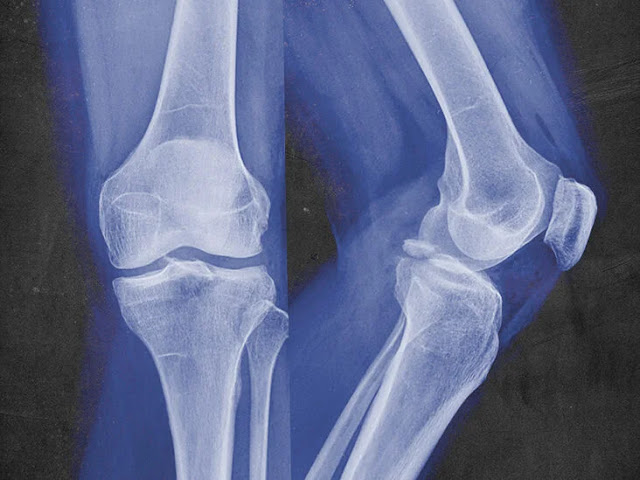

Μια μελέτη από το Πανεπιστήμιο Ulm, στη Γερμανία, αποκάλυψε τους μοριακούς μηχανισμούς με τους οποίους το ψυχολογικό τραύμα και άλλες μαζικά στρεσογόνες εμπειρίες επιβραδύνουν την επούλωση των καταγμάτων των οστών.

Τα σωστικά συνεργεία έκτακτης ανάγκης βιώνουν τεράστιο στρες, όπως και τα θύματα φυσικών καταστροφών και πράξεων βίας. Σε περίπτωση σοβαρού τραυματισμού, αυτό δεν μένει χωρίς συνέπειες. Είναι ήδη γνωστό ότι οι μαζικά στρεσογόνες και τραυματικές εμπειρίες επιβραδύνουν την επούλωση των πληγών και των οστών. Ερευνητές στο University Medical Center Ulm ανακάλυψαν τώρα τον μοριακό μηχανισμό που κρύβεται πίσω από τις αρνητικές επιπτώσεις του άγχους στο μεταβολισμό και την αναγέννηση των οστών.